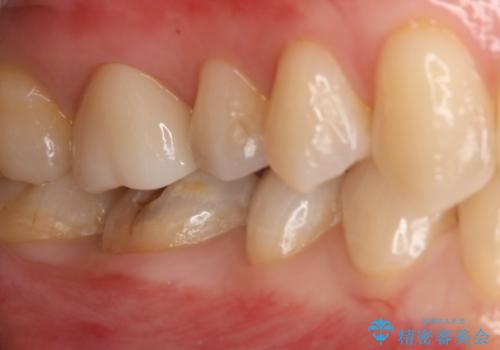

銀の詰め物が取れた セラミックインレー治療

- 右下6番のメタルインレー脱離のため来院。

セラミックの治療を希望されたため切削量を考慮し、セラミックインレーでの治療を選択しました。

う蝕が深くまで進行していたので、CRで裏層した上で形成・印象をしています。